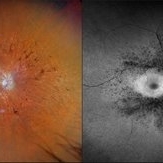

Exudative Retinal Detachment

Exudative Retinal Detachment

Aug 6 2025 by Aditya S Kelkar, MS, FRCS, FASRS,FRCOphth

Fundus auto-fluorescence of a 41 year old female depicting retinal pigment epitheliopathy and exudative retinal detachment in case of ocular metastasis secondary to breast carcinoma.

Photographer: Dr.Rabia Naaz, National Institute of ophthalmology, Pune

Imaging device: OPTOS DAYTONA

Condition/keywords: Exudative retinal detachment, Retinal pigment epitheliopathy